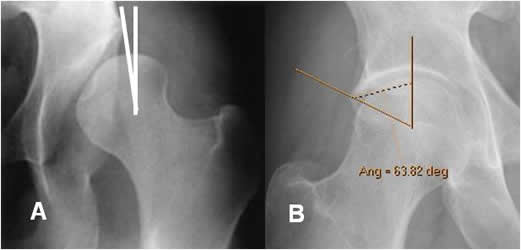

Fig 60 A. Anteversión femoral anormal.

Incremento del ángulo, en un paciente con parálisis cerebral.

Fig 60 B. Anteversión femoral anormal.

Medición del ángulo con el software de la máquina, el cual está aumentado.